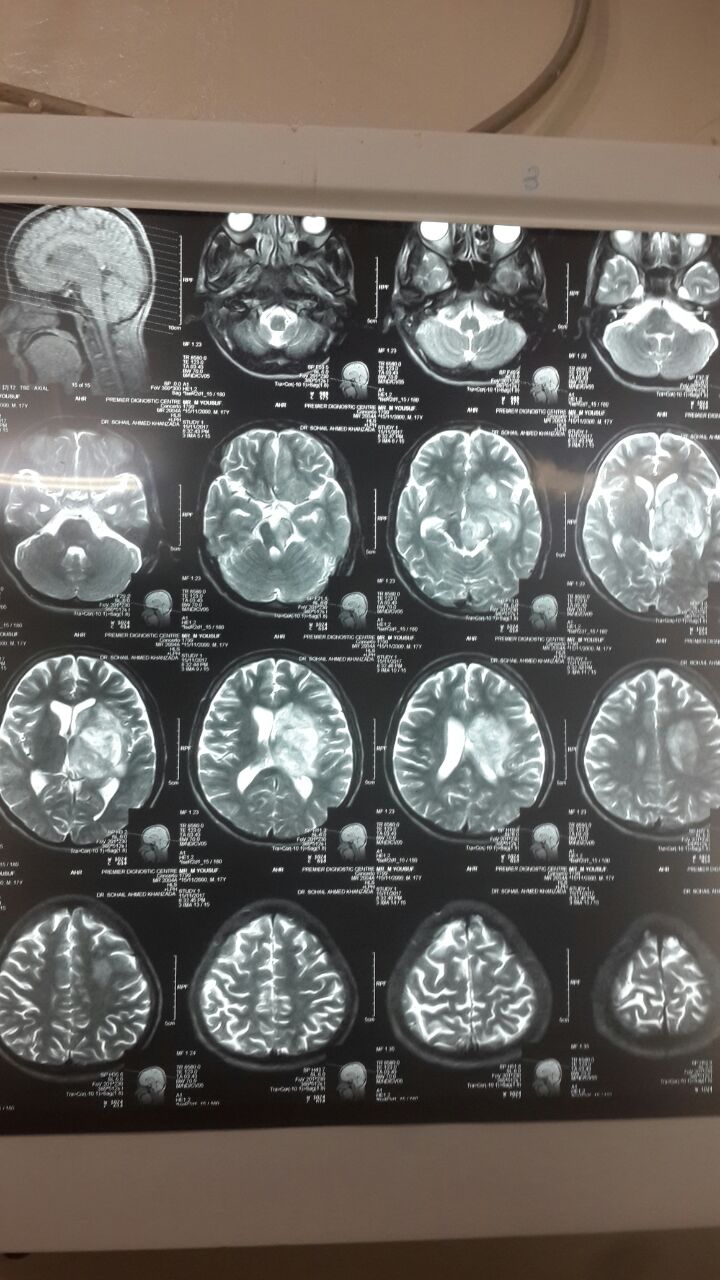

Case#151

17 years old..

Hx of high grade fever 7 days back

Pt consious. .Aphasic.

6th and 7th nerve palsy

Rt side hemiplegia. .